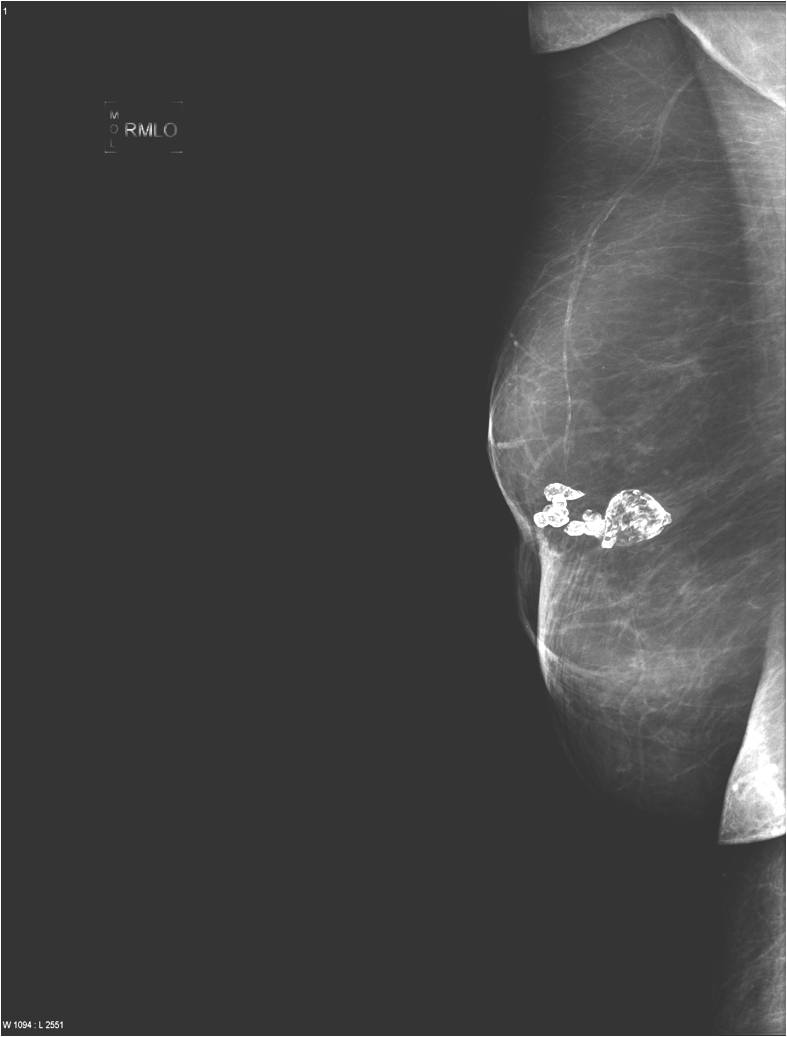

2. Digital mammography has displaced the analogue technic for today almost everywhere: (pictures 1,2,3) phosphorous plate or direct digital methods. For breast imaging the latter is the method of choice. Phases of image production separate. The image is produced on the detectors, but appears on the high resolution monitor and can be stored as a digital data set at various storage mediums (e.g.: CD, hard disk drives).

Image

Picture 1.

Picture 2.

Picture 3.